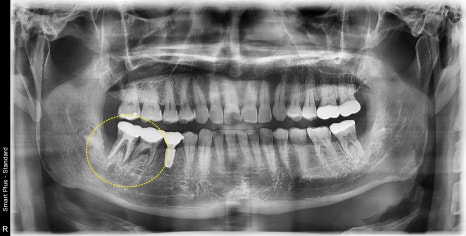

예를 들어

이렇게 사진상 진단시는 발치와 동시에 임플란트 수술이

가능했지만 제때 치료 시기를 놓치게 되면

시간이 지나 주변 뼈들이 염증에 의해 더 녹아

발치 후 치조골이식을 진행한 후

회복후 수술이 필요한 경우도 있습니다

노란 원으로 표시된곳이 치조골이식후 회복된상태입니다

물론 결과적으로 치료가 잘 마무리가 되지만

치료시기를 놓치게 되면 치료기간이 2배로 늘어날수 있습니다.